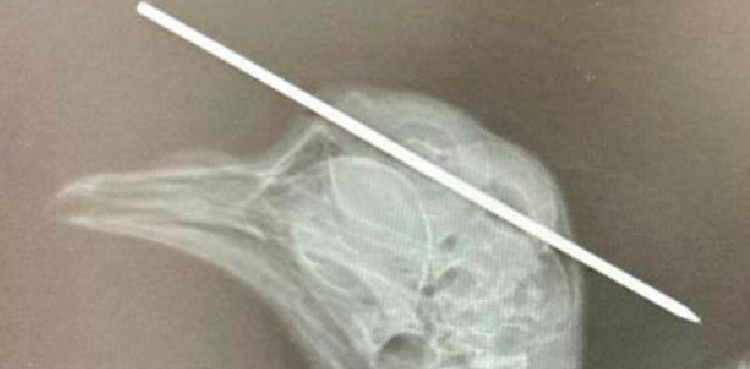

A pigeon who has been named ‘Dardo’ was found with a syringe needle that went through its head, he was caught by an animal lover who wanted the bird’s misery to end.

It is believed that Dardo was a victim of a cruel human who shoved the needle into his head, but the little bird miraculously survived surgery to remove the impaling needle.

A three-inch syringe needle went through the front of the bird’s skull and out through the other side but has now been saved and let out back into the wild.